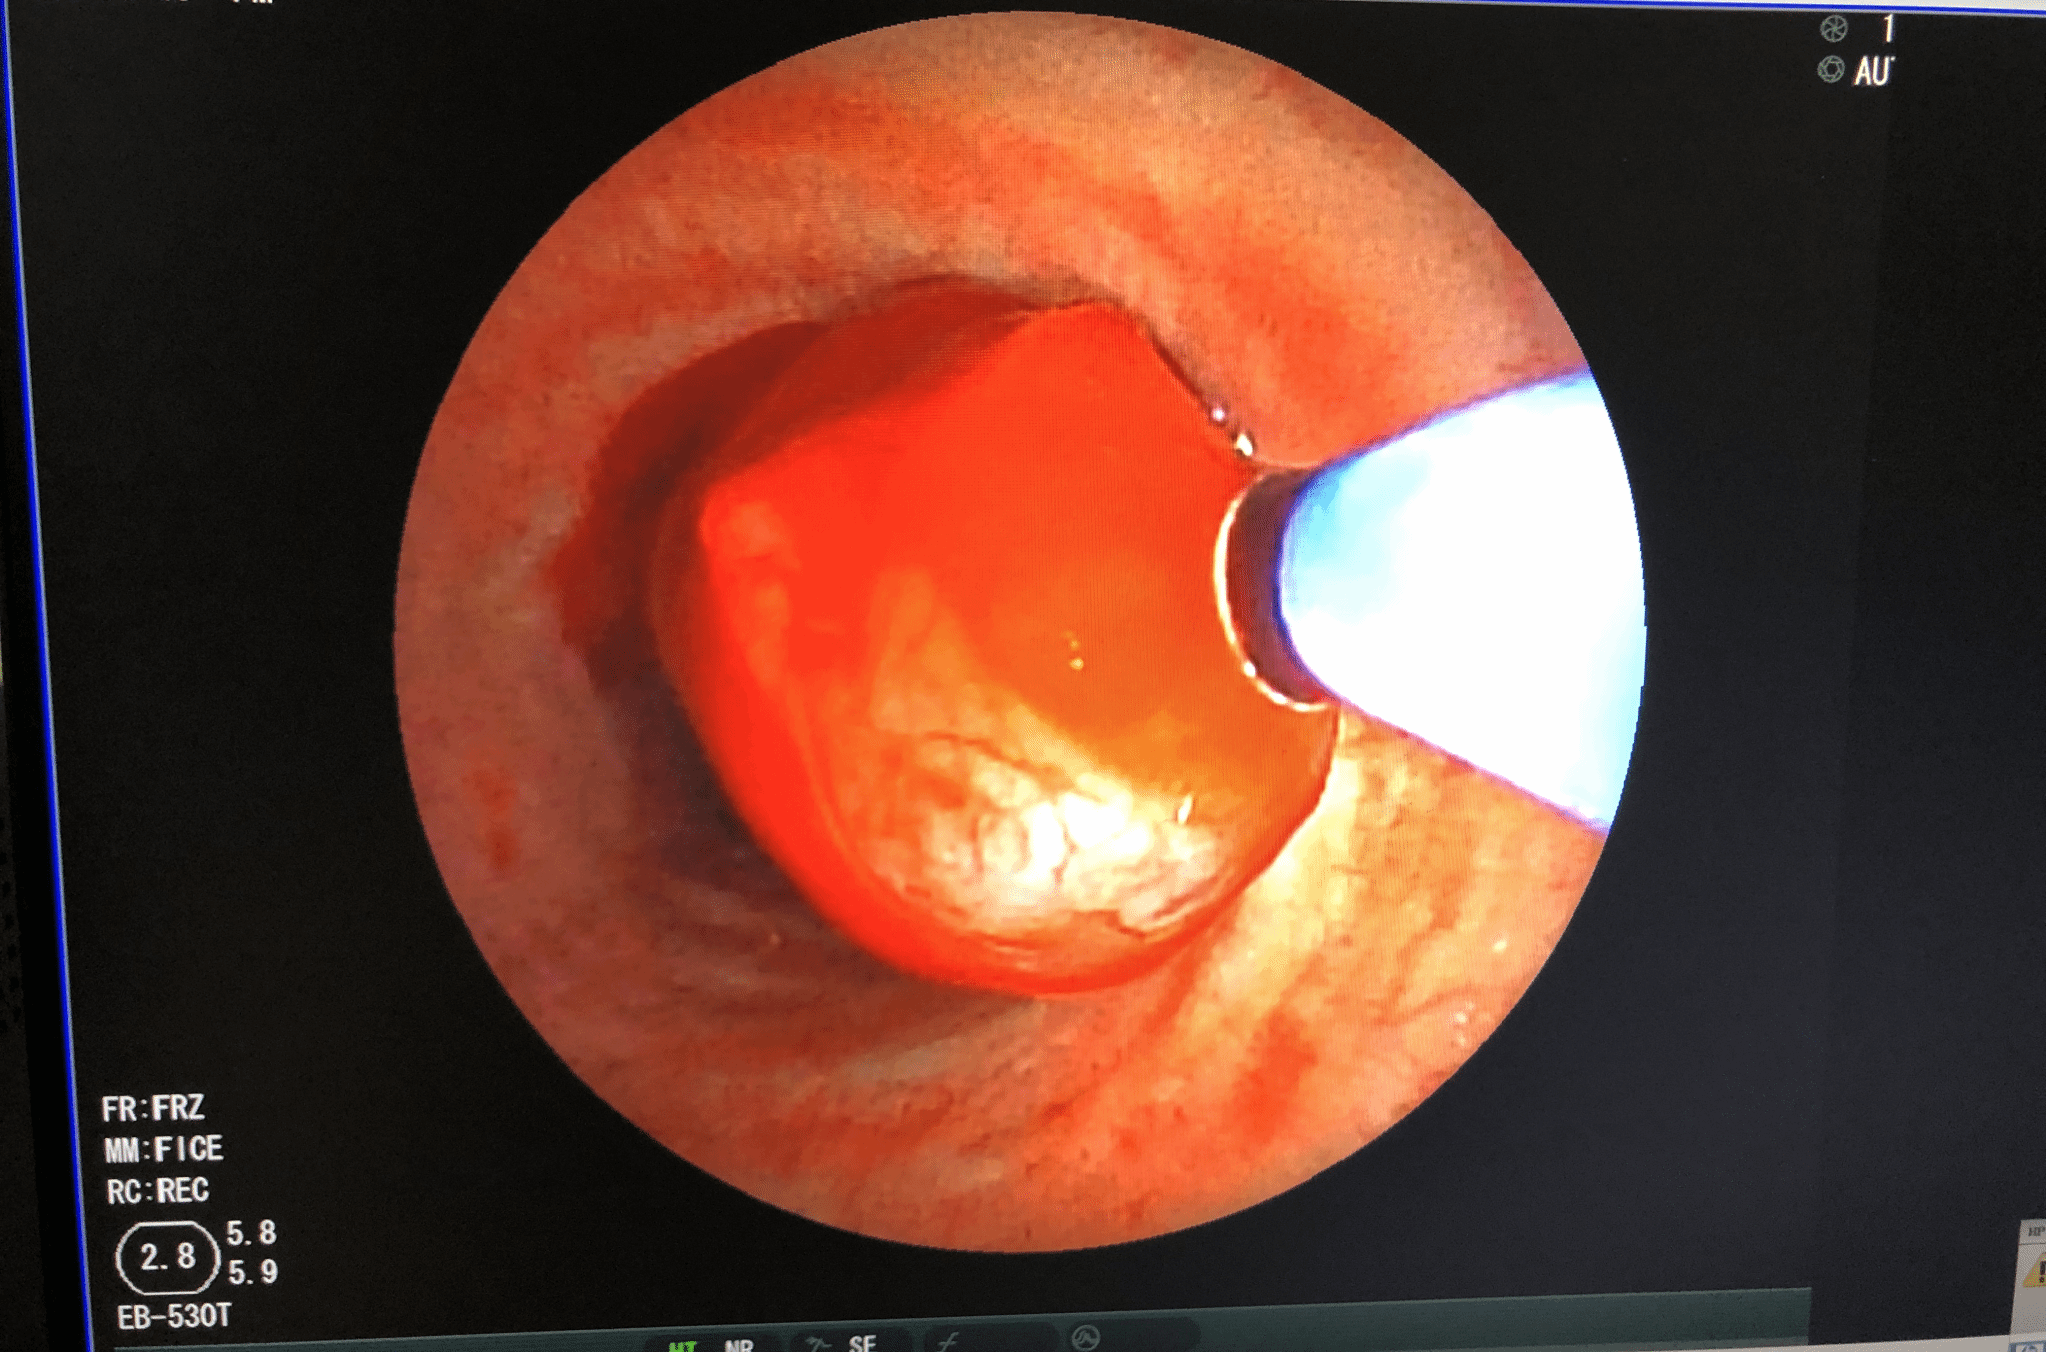

冷冻治疗术

冷冻治疗前 冷冻治疗中